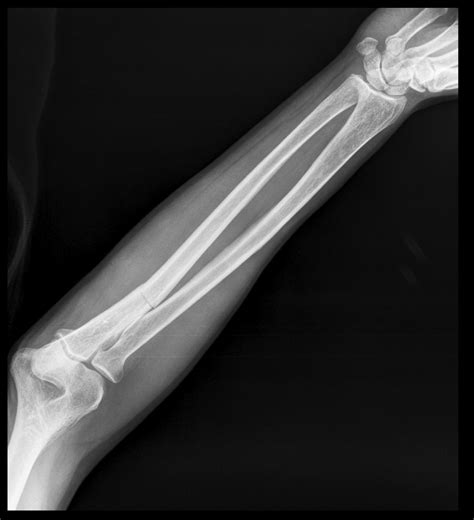

Xray Of Bone Fracture

Bone fractures are a common injury that can occur due to various reasons such as accidents, falls, or sports injuries. An accurate diagnosis is crucial for effective treatment, and one of the most reliable methods for diagnosing bone fractures is through an X-ray of bone fracture. This non-invasive imaging technique provides detailed images of the bones, helping healthcare professionals to assess the extent of the damage and plan appropriate treatment.

An X-ray of bone fracture is a critical diagnostic tool that provides a clear view of the bone structure. This imaging technique uses electromagnetic radiation to produce images of the inside of the body. When it comes to diagnosing bone fractures, X-rays are particularly useful because:

Types of Fractures Visible on X-rays

X-rays can detect a wide range of fractures, including:

• Simple Fractures: These are clean breaks with minimal displacement.

• Displaced Fractures: These occur when the bone fragments are separated and not aligned.

• Impacted Fractures: These happen when one bone fragment is driven into another.

• Comminuted Fractures: These involve multiple bone fragments.

• Pathological Fractures: These occur in bones that are already weakened by disease, such as cancer or osteoporosis.